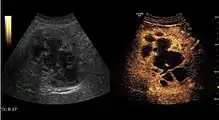

Encephaloid hepatocellular carcinoma (CEUS). Contrast tumor enhancement is observed on the left during arterial phase. The “wash-out” phenomenon can be seen on the right, during portal venous phase.